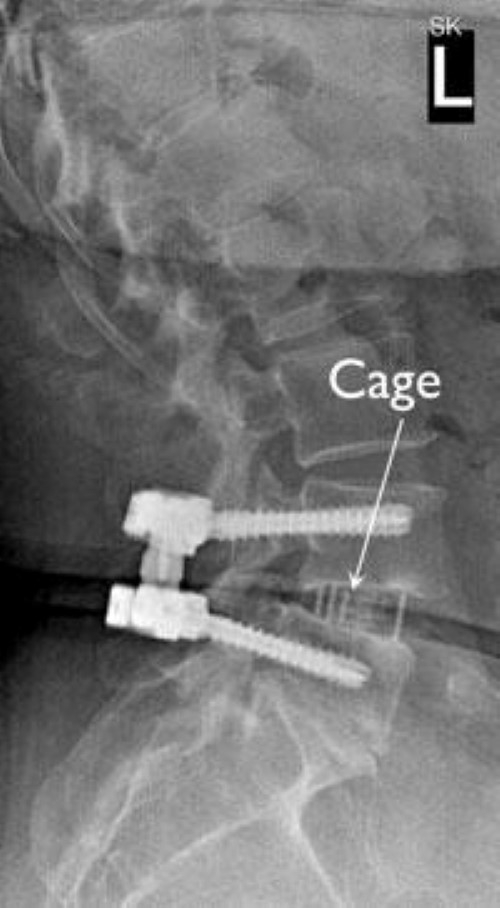

x-ray of cage and screws for interbody fusion

This X-ray taken from the side shows the cage between the vertebrae and screws that are stabilizing the spine.